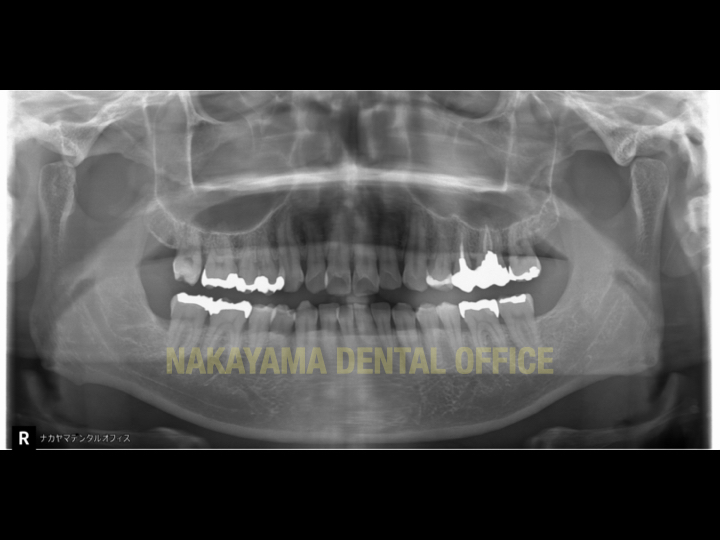

症例写真(当院での実際の症例)

銀歯の下のむし歯

左(治療前):つい最近、他院での検診ではむし歯はありませんと言われたばかりでした。確かに一見むし歯は無いように思われます。

右(レントゲン画像):金属の中の状態はレントゲンには写らないのですが、良く観察すると金属と歯の間にごくわずかな隙間があります。